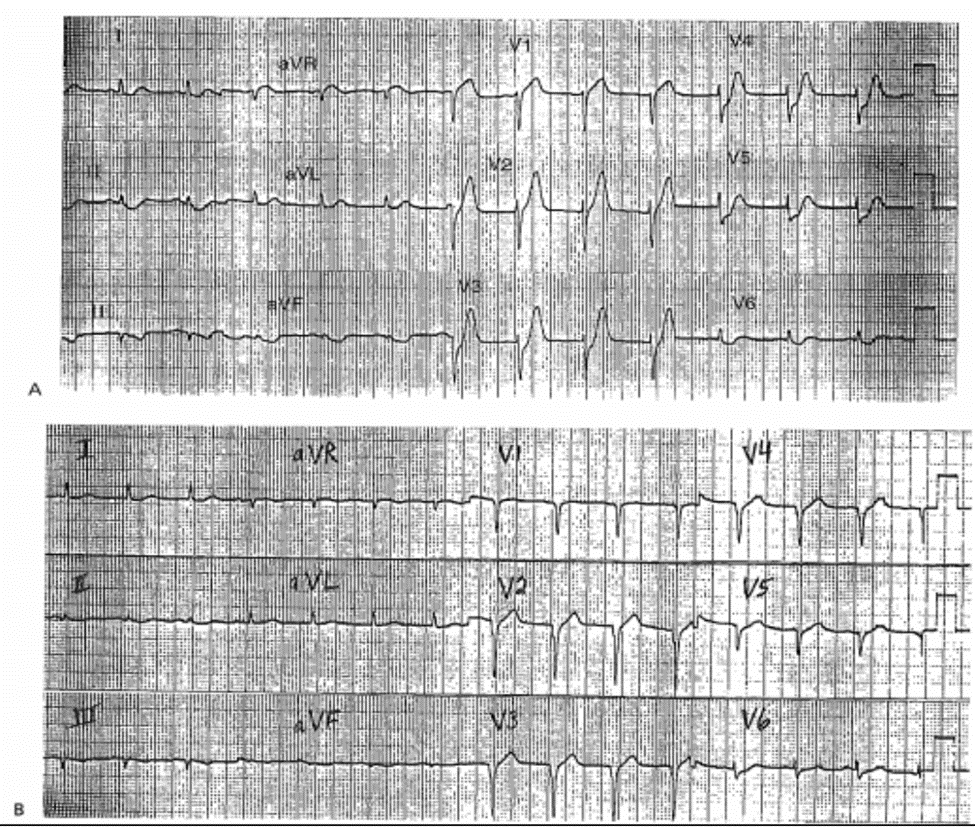

ECG 9-6A (Type 2)

Ghi lúc 10:40, 40 phút sau khi đến

■ Sóng T lớn, không cân đối: V2 – V4; và ST chênh xuống V2 – V6 , nghi ngờ AMI thành trước. Ghi chuỗi ECG sau đó được chỉ định.

Diễn biến lâm sàng

Bác sỹ đã không nghi ngờ đây là AMI và không cho làm chuỗi ECG. Bệnh nhân đã vào CCU. Mặc dù tPA đã được dùng sau 5,25 giờ kể từ khi khởi phát đau. ECG 9-6B Bênh nhân đã được xác định có AMI thành trước rộng với sóng Q sâu ở V1 – V5. Siêu âm tim thấy bất thường vận động mới vùng trước vách và mõm tim.

Kết Luận

Sóng T cao cấp tính có xảy ra sau khi ST chênh xuống (xem Case ECG 9-7A). Chẩn đoán và tiêu huyết khối đối với AMI thành trước rộng bị trì hoãn nhiều giờ bởi đoạn ST và sóng T không được đánh giá đúng. Ghi lại ECG sớm được chỉ định

ECG 9-7A (Type lb)

■ ST chênh lên: nhỏ, chỉ ở V1; và sóng T cao cấp tính rõ: V2-V3 chẩn đoán là AMI thành trước

ECG 9-7B (Type la)

12 phút sau

■ ST chênh lên: V2—V4; khó thấy nhưng chẩn đoán là AMI thành trước.

ECG ghi 27 phút sau đó có ST chênh lên ở đạo trình thành trước 4mm. Tiêu huyết khối dẫn đến tái tưới máu thành công, có sự tăng nhẹ CK – MK và không có biến chứng.

Sự nghi ngờ của bác sỹ đối với AMI và xác định bằng ghi chuỗi ECG giúp sử dụng tiêu huyết khối đúng lúc và sự phá hủy cơ tim ít nhất.